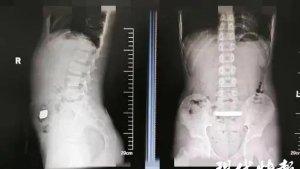

Setelah mengetahui bahwa itu adalah kehamilan ektopik, dia memutuskan untuk mengakhiri kehamilannya dengan aborsi.

Kehamilan ektopik dapat menyebabkan nyeri perut, pendarahan hebat, dan bahkan syok, dan biasanya memerlukan pengobatan atau pembedahan.

Chen membawa istrinya ke rumah sakit, di mana dia menjalani operasi yang menghabiskan biaya lebih dari US$ 1.400 (sekitar Rp 22 juta).